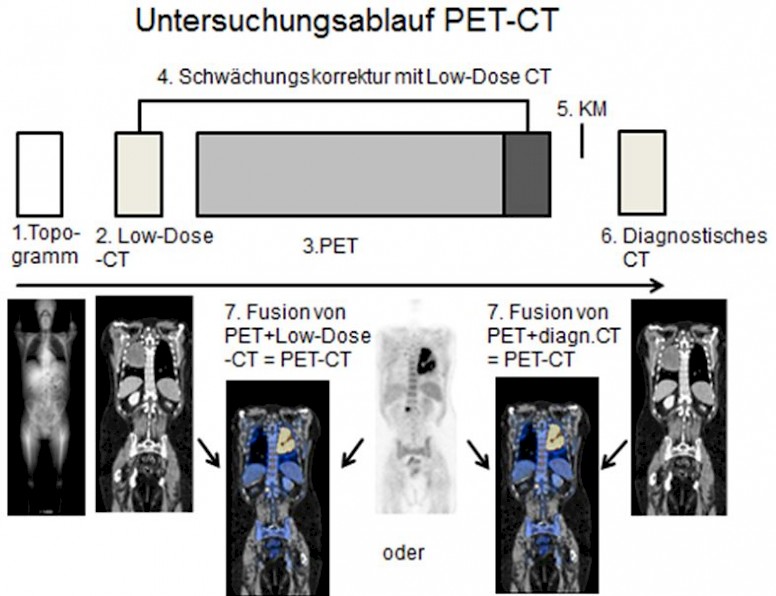

- Zunächst wird ein CT-Topogramm des Patienten angefertigt anhand dessen die anatomischen Aufnahmebereiche der CT und der PET festgelegt werden.

- Dann folgt eine native CT-Untersuchung in Low-Dose Technik des gesamten Untersuchungsbereiches, meist von der Schädelbasis bis zur Mitte beider Oberschenkel.

- Dann erfolgt die PET-Untersuchung. Diese ist meist in 8 bis 9 Bettpositionen unterteilt.

- Mit dem Low-Dose-CT wird eine Schwächungskorrektur der PET-Daten vorgenommen, um Schwächungseffekte im aufgenommenen Körper herauszurechnen.

- Bei entsprechender klinischer Indikation schließt sich eine Normaldosis-CT mit KM einer ausgewählten Körperregion, zum Beispiel des Thoraxes an.

- Zuletzt werden die schwächungskorrigierten PET-Daten mit den CT-Daten fusioniert und ergeben den PET-CT-Datensatz.